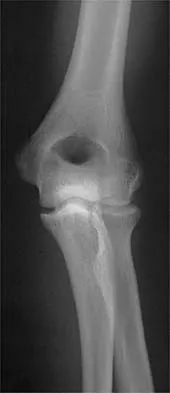

Figure 31 shows the AP and lateral radiographs of the elbow of a 56-year-old man with chronic polyarticular rheumatoid arthritis. His function continues to be limited by pain with activities of daily living. Examination shows that his total arc of motion is 110 degrees. Nonsurgical management has failed to provide relief. Treatment should now consist of

A semiconstrained prosthesis can provide excellent results in carefully selected patients. Because the radiographs show extensive joint destruction with loss of the capitellum and trochlea, a capitellocondylar total elbow (unconstrained) prosthesis is contraindicated. Elbow fusion is poorly accepted, and the radiographs show too much articular destruction for a radial head excision, synovectomy, or interposition arthroplasty to be effective. Ewald FC, Simmons ED Jr, Sullivan JA, et al: Capitellocondylar total elbow replacement in rheumatoid arthritis: Long-term results. J Bone Joint Surg Am 1993;75:498-507.